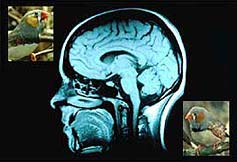

A leafy suburb in upstate New York is the unlikely setting for pioneering research into the human brain. But at his field research centre, scientist Fernando Nottebohm is using song birds like the canary, to unlock the secrets of how we remember and why we forget.

It used to be thought that babies are born with all the brain cells they would ever need - more than a hundred billion of them - and that as one ages, these cells start dying off irreversibly until death. But in the early 1980s, one scientist discovered that canaries grew new brain cells in order to learn the new mating songs they need each spring. Fernando Nottebohm wondered how they managed to do this and to his and the world's amazement discovered that the bird's brain grew and then shrank according to its behaviour. Eventually, other animals were found to have the ability to increase the size of their brains at will - rats, monkeys and finally, in the late 1990s, even the human adult brain showed small signs of new cell creation or “neurogenesis”.

Surrounded by more than 5000 canaries and 1500 Zebra Finches, Nottebohm and his team are teaching birds to sing new songs and analysing how their brains are acquiring this new information. As Rami Tzbar reports, they hope to discover whether this process can be 'turned on' in humans and used to slow down and maybe even reverse the progression of chronic and incurable conditions like Alzheimer's and Parkinson's disease. Alcohol and Error-Prone Thinking